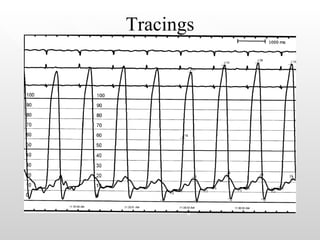

Tracings

What is the differential diagnosis for these tracings? How do we make the diagnosis?